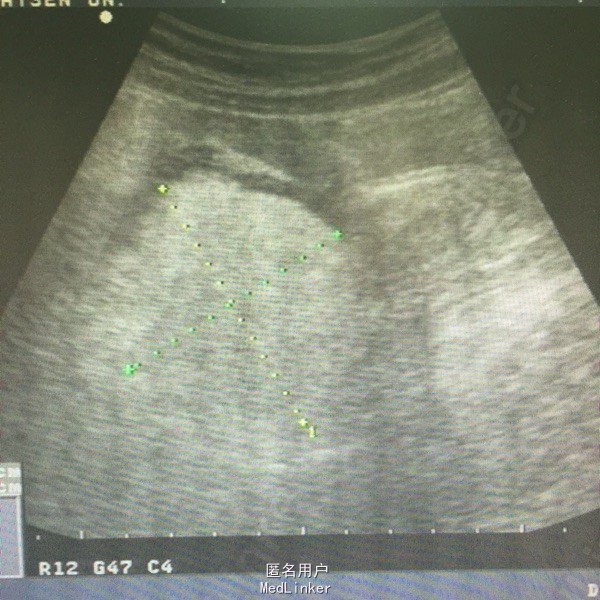

肛查:双侧附件区个扪及一肿物,右侧6*6cm,无压痛、反跳痛,左侧3*3cm,有压痛,无反跳痛。阑尾彩超未见明确显示。血常规白细胞及中性粒细胞百分率升高。彩超子宫双附件:双侧附件区混合性肿块,右侧60*54mm,左侧38*21mm,呈面团征,后方回声增强,考虑畸胎瘤可能性大。

诊断:双侧卵巢畸胎瘤,左侧卵巢蒂扭转。行腹腔镜检查,术中见右侧输卵管扭转180°,卵巢表面血运良好,予行双侧卵巢囊肿剔除,标本中查见毛发及油脂。术后病理:双侧卵巢成熟性畸胎瘤。

卵巢畸胎瘤部分患者为双侧,因密度不均,常因活动或体位改变后发生蒂扭转,因此一经发现就有手术指征。